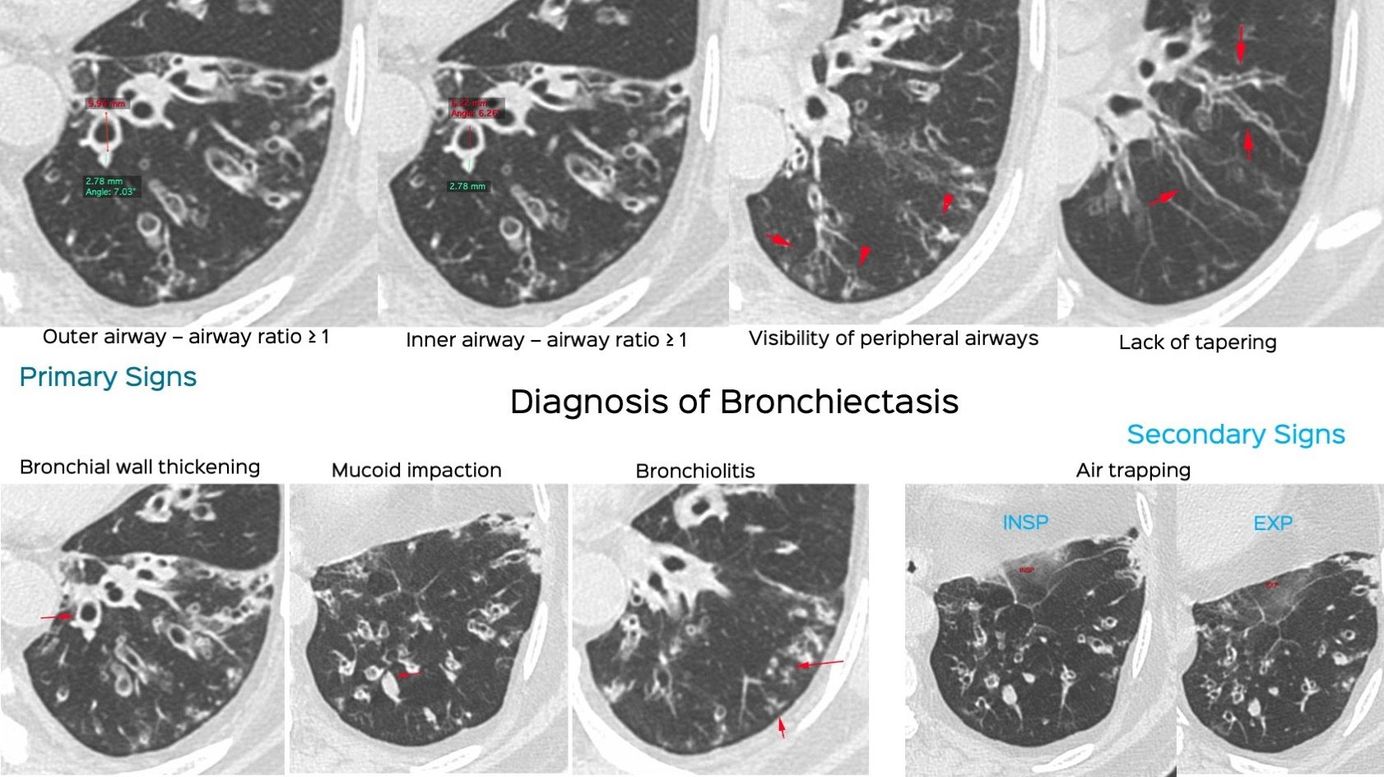

Snippet 10: Diagnosis of Bronchiectasis Paid Members Public

The primary and secondary signs of bronchiectasis on CT scan